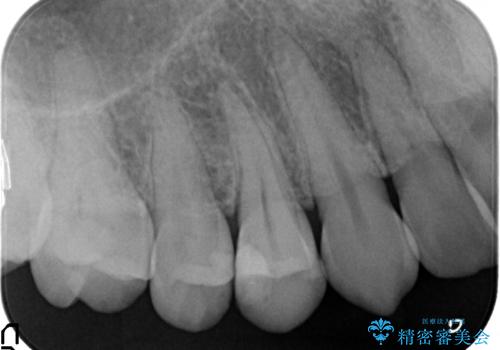

検査の結果、右上4番目の歯は神経が死んでおり、そのせいで歯茎に膿の出口が出来ていることがわかりました。

右上4は根管治療を行い、オールセラミッククラウンによる補綴を行いました。